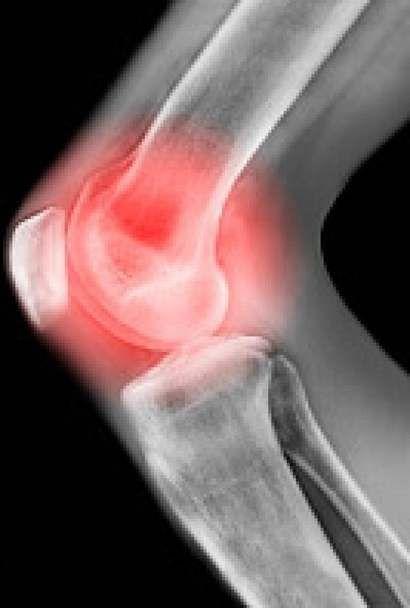

感染性关节炎症状?

第一:对称性疼痛,对称性疼痛是因为关节炎的病变可同时侵及双侧肢体的相同关节,例如双膝、双肘关节可同时发生疼痛。

第二:游走性疼痛,游走性疼痛跟对称性不太相同,指的是一个关节的疼痛好转后或还未明显好转,另一关节又受到侵袭,发生疼痛。

第三:关节异常,风湿性关节炎的症状可为关节疼痛时伴有发红、肿胀、关节周围有压痛、拒按。